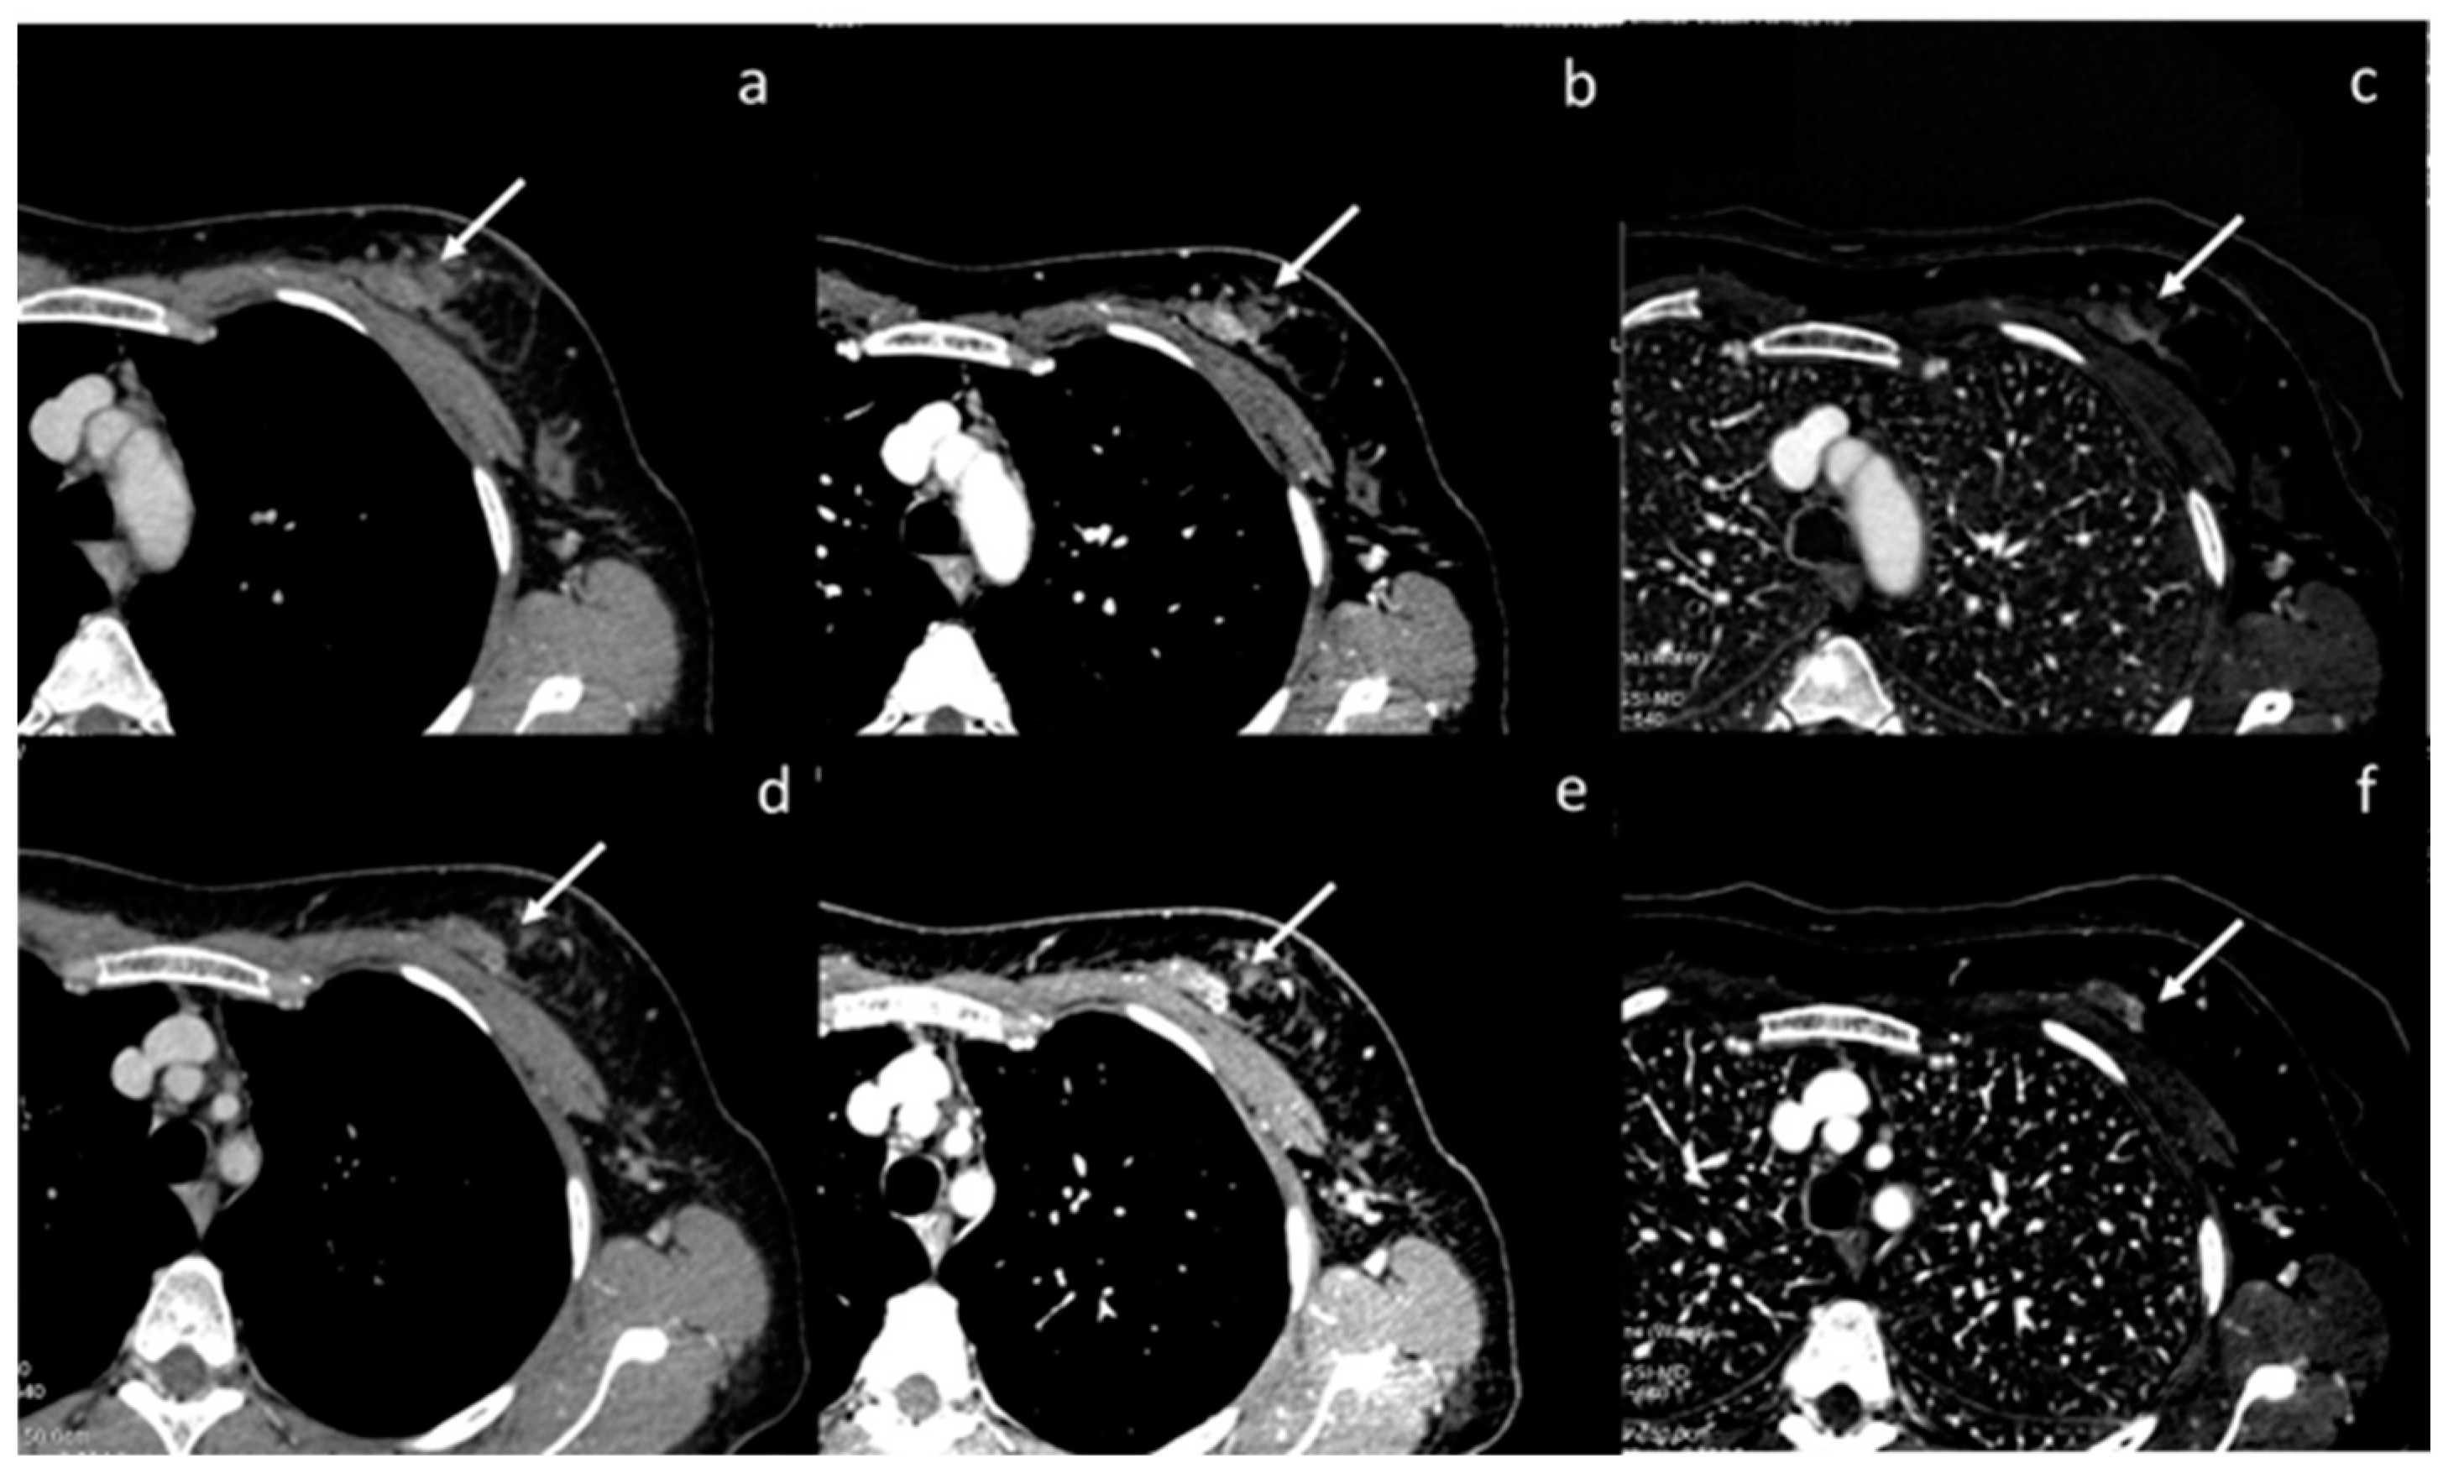

- Cheng, F.; Liu, Y.; Du, L.; Wang, L.; Li, L.; Shi, J.; Wang, X.; Zhang, J. Evaluation of optimal monoenergetic images acquired by dual-energy CT in the diagnosis of T staging of thoracic esophageal cancer. Insights into Imaging 2023, 14, 33. [Google Scholar] [CrossRef]

- Zopfs, D.; Hokamp, N.G.; Reimer, R.; Bratke, G.; Maintz, D.; Bruns, C.; Mallmann, C.; Persigehl, T.; Haneder, S.; Lennartz, S. Value of spectral detector CT for pretherapeutic, locoregional assessment of esophageal cancer. Eur. J. Radiol. 2021, 134, 109423. [Google Scholar] [CrossRef] [PubMed]

| Cheng et al. [65] Retrospective study | China | To objectively and subjectively assess optimal VMI characteristics from DECT and the diagnostic performance for the T-staging in patients with thoracic esophageal cancer | 68 | SOMATOM Drive, Siemens Healthineers No C.I. | DECT has great advantages in evaluating T-staging in patients with EC. The venous phase VMI40 keV can improve the accuracy of evaluating T- staging, and quantitative parameters derived from DECT also can help to identify T1-2 from T3-4. |

| Zopfs et al. [66] Retrospective study | Germany | To investigate the diagnostic value of spectral detector DECT-derived low-keV VMI and iodine overlays for locoregional, pretherapeutic assessment of esophageal cancer | 74 | IQon, Philips Healthcare, Best, The Netherlands) No C.I. | Virtual monoenergetic images at 40–60 keV improve qualitative assessment of the esophageal cancer lesion and depiction of lymph nodes and vessels at pretherapeutic. |